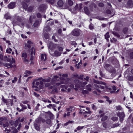

To deal with some of the aforementioned issues, we introduce a new approach for simultaneous H&E stain normalization and augmentation based on the multimarginal Wasserstein barycenter approach. Specifically, the novelty of the paper lies in first introducing the traditional Wasserstein barycenter approach for stain normalization/augmentation (Figure 1), and then introducing the multimarginal version [1, 9] to overcome the limitations of the traditional approach in this context (Figure 2). Note that the traditional Wasserstein barycenter (1 source and 1 reference), although widely employed in computer vision, to the best of our knowledge has never been used for stain normalization/augmentation and the more general multimarginal Wasserstein barycenter (1 source and multiple references) has hardly ever been used in computer vision or medical imaging communities. For more accurate stain normalization, the multimarginal version allows one to incorporate additional distributions by utilizing one or more intermediate reference images (Figure 2). The resultant interpolations span a broad spectrum of stain variations allowing for simultaneous stain normalization and augmentation.

We used MITOS-ATYPIA’14 challenge dataset for evaluating our stain normalization. The dataset includes same tissue sections scanned by two different scanners (Aperio-A and Hamamatsu-H) with total 424 X20 A-H frame pairs, 300 training and 124 testing. Images from scanner A are normalized and matched against the real corresponding images from H (ground truth). As in StainGAN [14], 10,000 random (256256) patches from 300 training frames were used for training (26 epochs with the regularization parameter , learning rate 0.0002, Adam optimizer with a batch size of 4) and 500 patches from 124 testing data used for evaluation. The visual and quantitative comparisons are shown in Figure 3 and Table 1, respectively. For the traditional case (one reference and source), our results are very similar to Reinhard et al. [12] since they also do color matching in Lab space, but our results improve drastically given two reference images. The references in our case span patches with different amounts of background visible. We also tested with different reference images and we show that we get a tighter bound as long as the references contain different amounts of background visibility; see Figure 4 for the box plots of SSIM for different references.